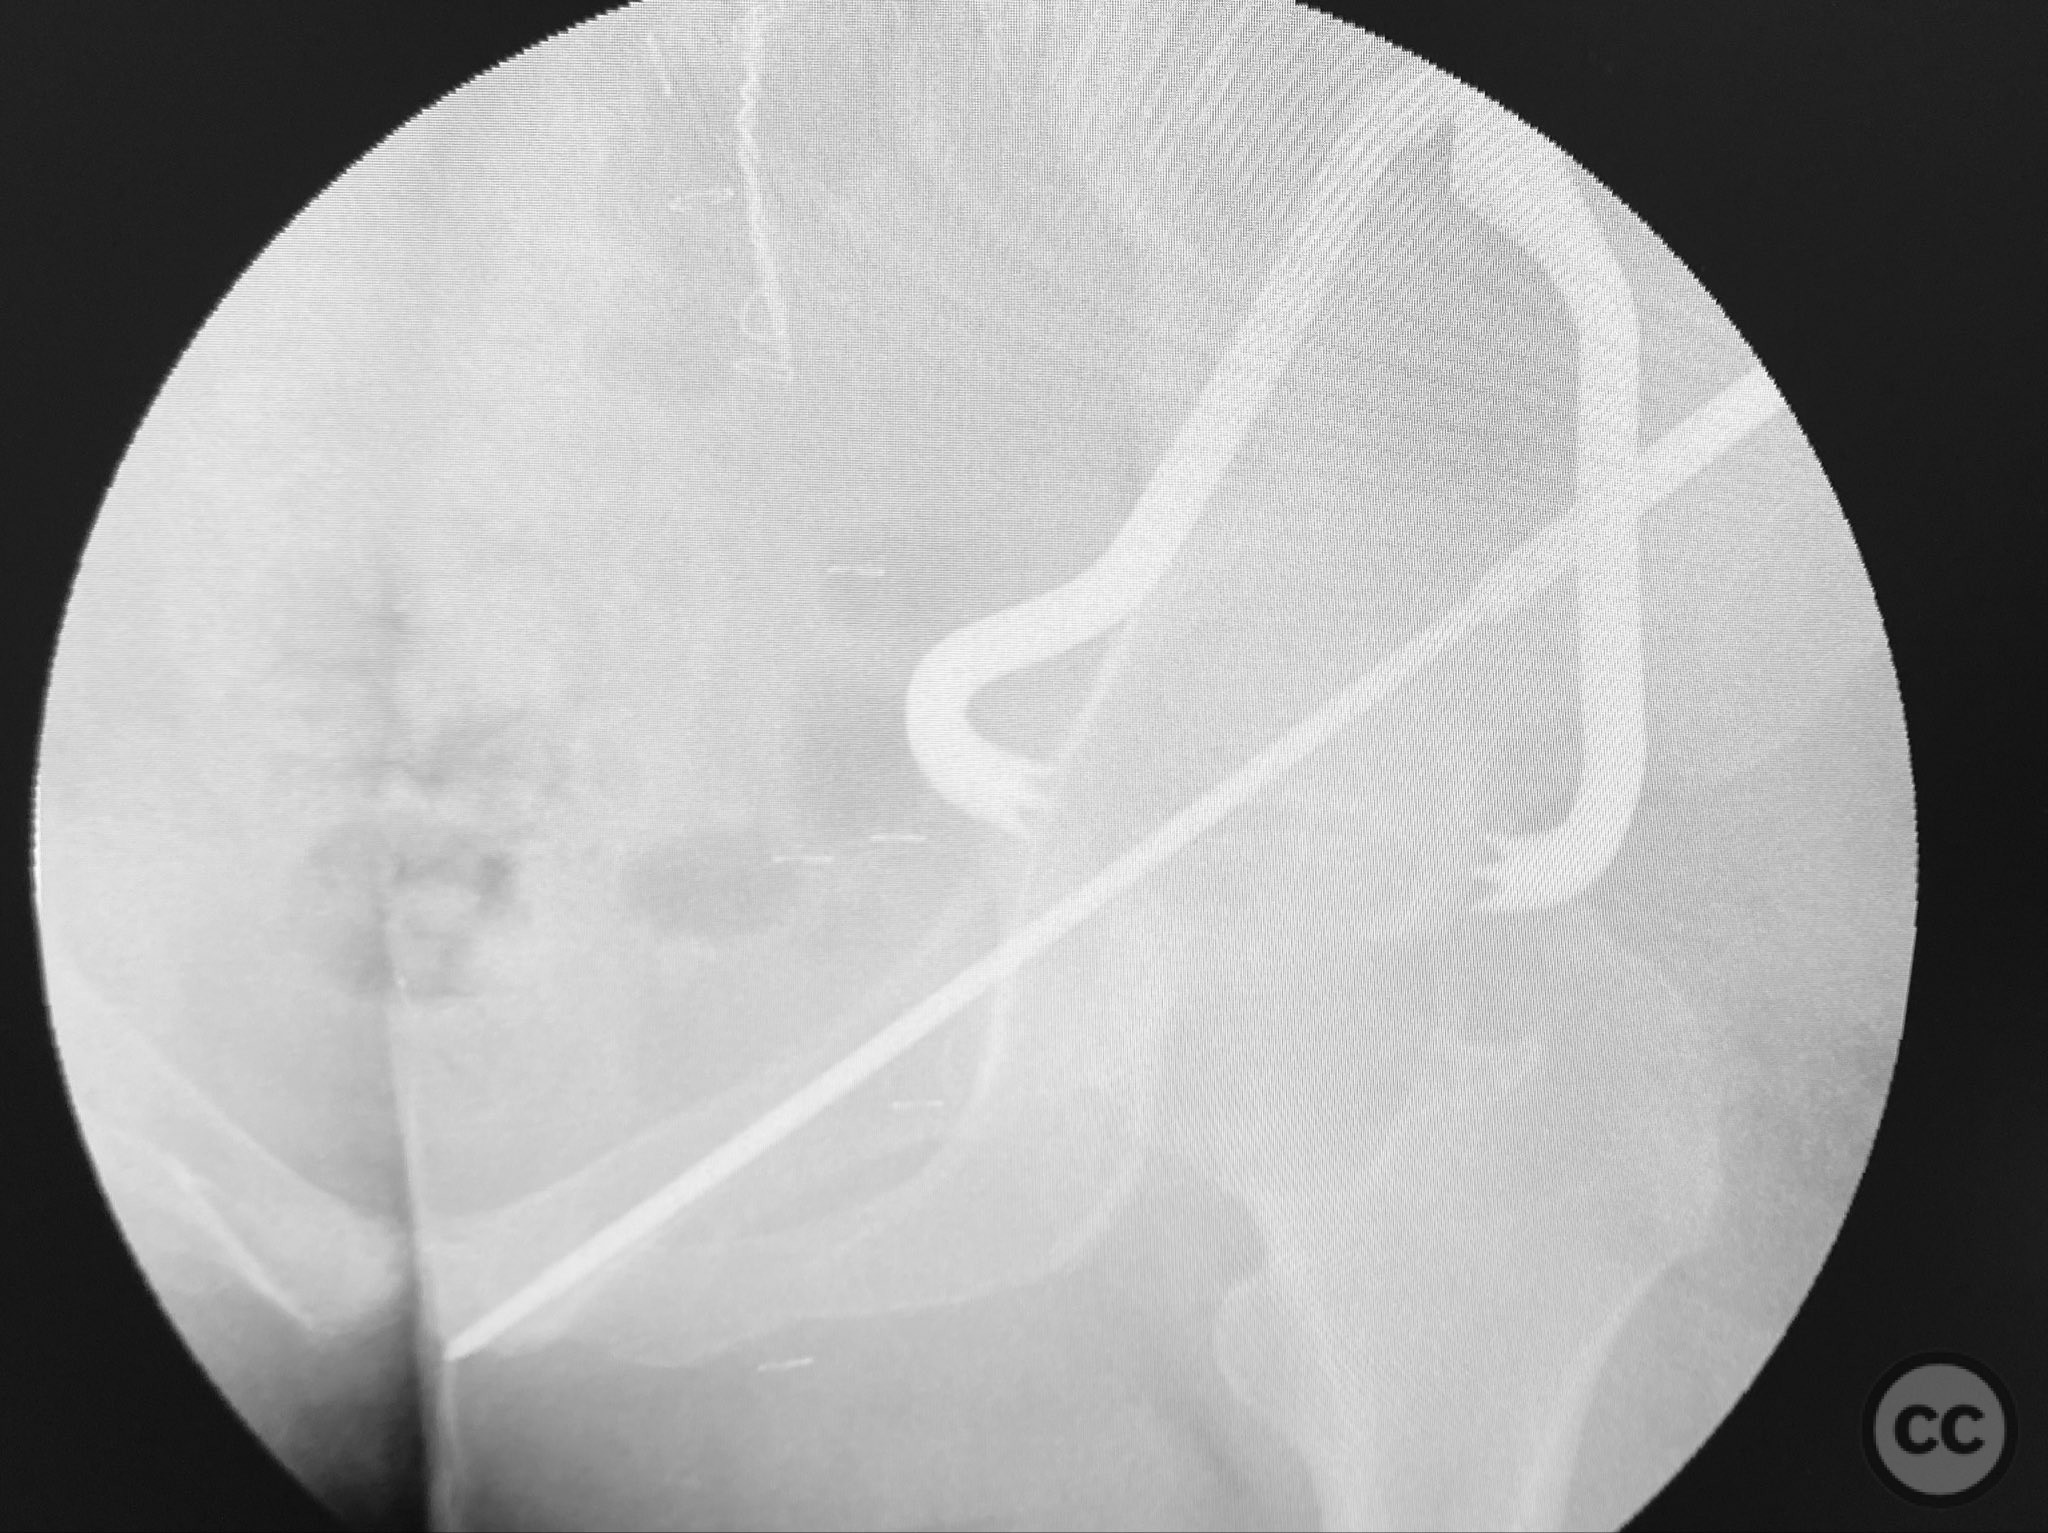

Clinical and radiological findings:  A high-speed motor vehicle collision resulted in a closed transverse acetabular fracture with associated comminuted posterior wall (PW) fracture-dislocation. The femoral head exhibited impaction and comminution, with local cancellous bone crushed and the femoral head itself also sustaining compressive injury from the denser acetabular bone. Neurovascular examination was unremarkable. Initial CT imaging delineated the acetabular fracture planes, displacement, comminution of the posterior wall, femoral head impaction, and absence of soft tissue attachment to the caudal PW fragment.

Planning remarks:  The preoperative plan was for open reduction and internal fixation via a posterior approach, specifically a Kocher-Langenbeck (KL) exposure, to allow direct visualization and manipulation of the transverse fracture plane and posterior wall fragments. Percutaneous biplanar fluoroscopy-guided cannulated cancellous lag screw fixation was planned for the transverse component, with subsequent buttress plating of the posterior wall fragments.

Operative remarks:

The transverse fracture was manipulated and temporarily stabilized using a reduction clamp applied across the fracture plane. Under biplanar fluoroscopic guidance, a cannulated cancellous lag screw was percutaneously inserted to achieve interfragmentary compression across the transverse component. The reduction clamp was then removed. Posterior wall fragments were anatomically reduced and stabilized with contoured buttress plates spanning both the posterior wall and providing additional stabilization to the transverse component. Postoperative CT confirmed satisfactory reduction and fixation of both acetabular columns and restoration of articular congruity.